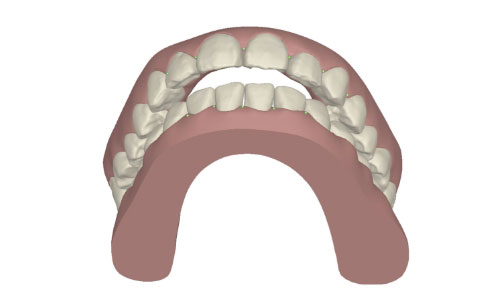

コンピューターを使って作製した透明なマウスピース型の矯正装置(アライナー)を段階的につけ替えていき、それにより歯列を矯正し、歯並びへと改善します。はじめに 治療開始から終了までのアライナーができあがってきます。マウスピース型矯正装置(インビザライン)の最大の特徴として「クリンチェック」というソフトがあります。3D のコンピュータ シュミレーション画像で、治療開始から完了までを目で見て確認することができます。

マウスピース型矯正装置(インビザライン)治療においては、クリンチェックというシミュレーションソフトを活用しております。

このクリンチェックの魅力は、治療前の現在の歯並びから治療後の歯並びを視覚化して患者様にご説明できる点にあります。

また、抜歯・非抜歯、全体矯正・部分矯正などそれぞれの治療パターンをシミュレーションすることが可能です。

| 治療前 |  |

| ライトプラン 隣接面削合なし |

| ライトプラン 隣接面削合あり |

| フルプラン 隣接面削合あり |